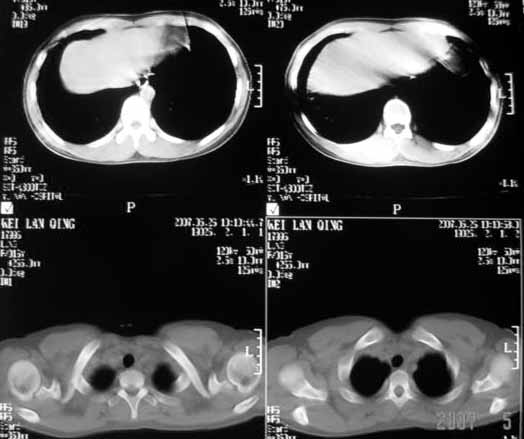

以下是引用dyqct在2007-5-26 12:01:00的发言:[br]右第二肋腋侧呈明显膨胀性、分叶状改变,内无明显间隔,ct值49hu,病变大小约67x57mm,周围硬化缘无断裂,内缘见多数骨嵴,肿块与正常骨间界限清楚。无移行带。周围软组织无浸蚀,胸膜腔无积液。[br]考虑:1、右第二肋动脉瘤样骨囊肿可能性大;[br] 2、需同骨巨细胞瘤、浆细胞瘤、骨纤鉴别。